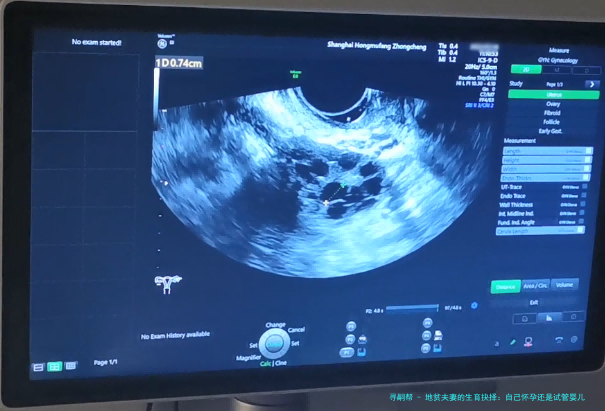

地贫夫妻的生育抉择:自己怀孕还是试管婴儿?

试管婴儿技术:现代医学的曙光

接下来,咱们聊聊试管婴儿技术。试管婴儿,学名叫体外受精-胚胎移植,特别是其中的PGD(植入前遗传学诊断)技术,简直就是地贫夫妻的救星。简单来说,医生可以在实验室里对胚胎进行基因筛查,只选择没有地贫基因的健康胚胎移植到子宫里。这样,就能大大降低孩子患病的风险。在我看来,这就像是为生育之路装上了“导航系统”,让你避开那些遗传陷阱。举个例子,前面提到的小张和小李后来选择了试管婴儿,通过PGD筛查,他们成功生下了健康的宝宝,现在家庭生活美满。不过,试管婴儿也有它的缺点,比如费用较高,过程可能比较繁琐,而且成功率不是100%。但总的来说,对于高风险的地贫夫妻,它提供了一个更安全的选项。